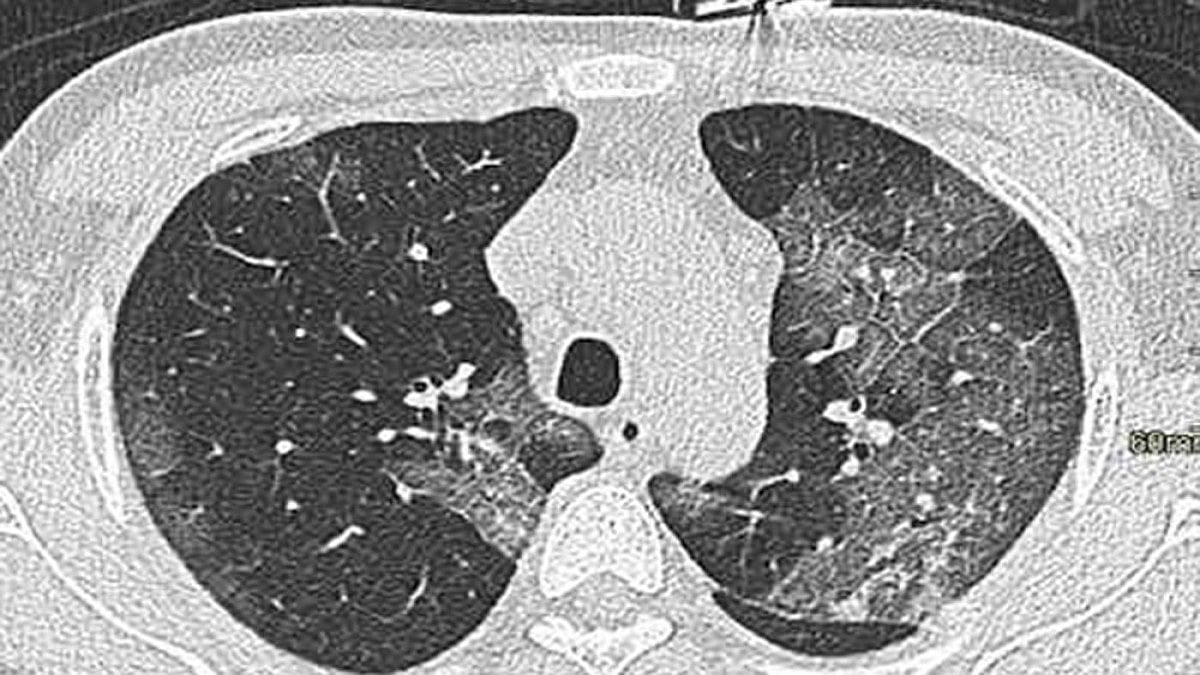

You know by now that the coronavirus doesn’t merely attack your lungs. But how does the presence of a whole axis of co-morbidities amplify the dangers? Here’s the science.